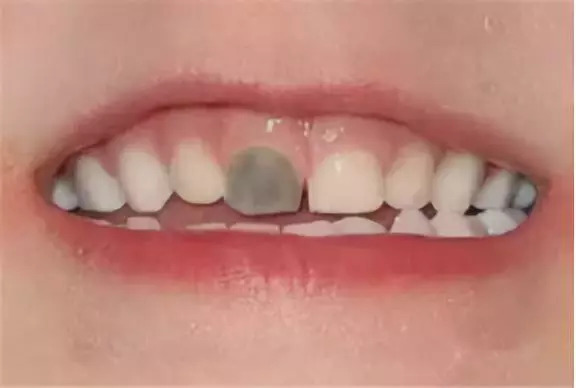

牙齿受伤:小宝宝走路跌跌撞撞的,碰伤了牙齿,可能会造成牙髓损伤,导致牙齿变得灰暗发黑。一旦发现宝宝的牙齿发生碰撞,一定要带宝宝去看牙医,检查情况。如果发现宝宝整颗牙齿变黑,一定要尽早带宝宝做牙齿检查,判断是否需要治疗。